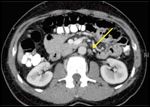

CT of the abdomen, demonstrating a positive retroperitoneal lymph node (delineated by arrows).

Postoperative staging CT evaluation of the chest, the abdomen, and the pelvis demonstrated an enlarged left retroperitoneal lymph node (0.8 × 1.2 cm), adrenal gland hyperplasia bilaterally, as well as gynecomastia (Figure 1).